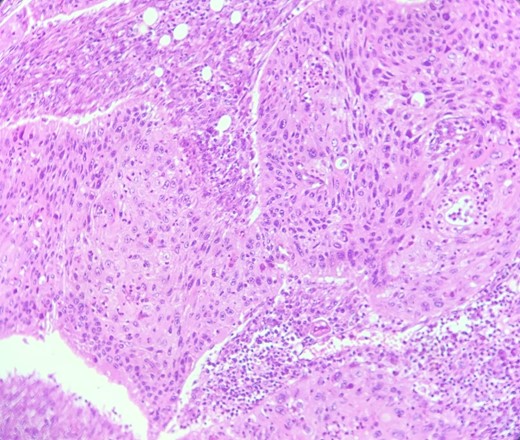

HE section: Neoplastic cells have densely chromatic enlarged nuclei with prominent nucleoli. They are enlarged with abundant eosinophilic cytoplasm and focal keratinization. Intercellular bridges are slightly visible (x200).